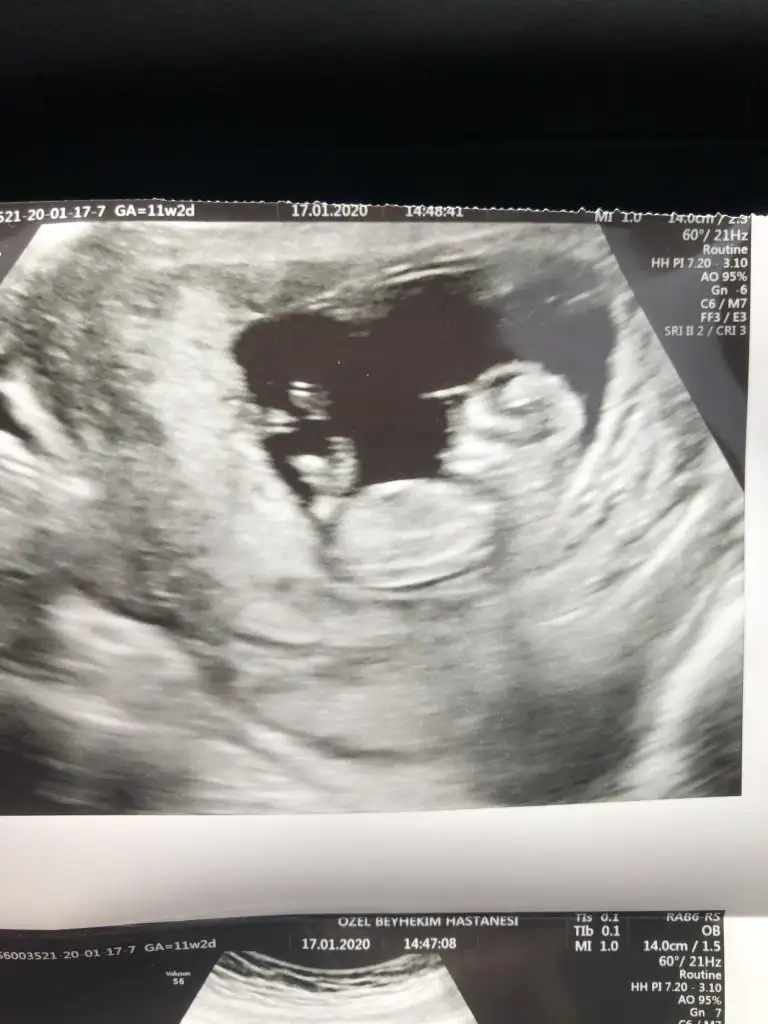

dr soylemeden siz gorun genital nub teorisi ( bebegin cinsiyeti)

11+6 yorumlarsan sevinirim 😂bu arada doktor birşey söyledi ama net değil.

Benim de 11+6 😍🧿 bana da yorum yapar mısın? Ikra meyra Ikra meyra